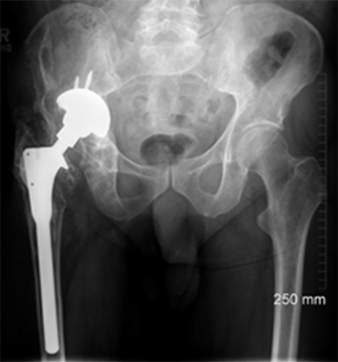

The patient, a 49-year-old woman, underwent metal-on-metal (MoM) hip resurfacing procedure in 2001 due to a unilateral hip dysplasia (DDH). 17 years later, she presented with mild hip pain but extensive loss of bone in the pelvis which was presumably caused by an inflammatory reaction to metal wear debris. Her blood metal ion levels were 100 times higher (cobalt 188 bbp and chromium 126 bbp) than from patients with well-functioning MoM hips.

The case posed multiple challenges. The patient was at imminent risk of pelvic fracture without surgery. However, surgery itself also risked fracture of the pelvis during implant removal. Furthermore, the remaining pelvic bone was poisoned by metal debris and thus the patient’s bone integrity was compromised, which could affect the stability of a new implant.

A multidisciplinary team decided that revision surgery was necessary due to the risk of fracture and very high metal ion levels. The plan involved removing the existing MoM implant and fitting a custom 3D-printed acetabular cup. The procedure required meticulous care to avoid causing fractures during implant removal. The new cup would only be effective if the pelvis remained intact.

The operation was successful, with minimal bone loss during implant removal. A custom-made titanium acetabular cup was fitted and stabilized with screws. Postoperative imaging confirmed correct implant positioning and satisfactory fixation. The patient’s recovery was positive, with significant reductions in metal ion levels and the restoration of pain-free hip function.

This case represents ALTR with MoM, which was characterized by extensive osteolysis of pelvic bone, which was presumably caused by metal wear debris. Elevated blood levels of chromium and cobalt further supported this hypothesis.

This case demonstrates the importance of precise surgical planning and execution in complex hip revision surgeries. The use of 3D-printed implants tailored to the patient's anatomy greatly improved the chances of successful fixation despite significant bone loss. Update at 6 years post operative is that the patient living a full and active life with excellent hip function. More details about this type of surgery has been published by Professor Hart: